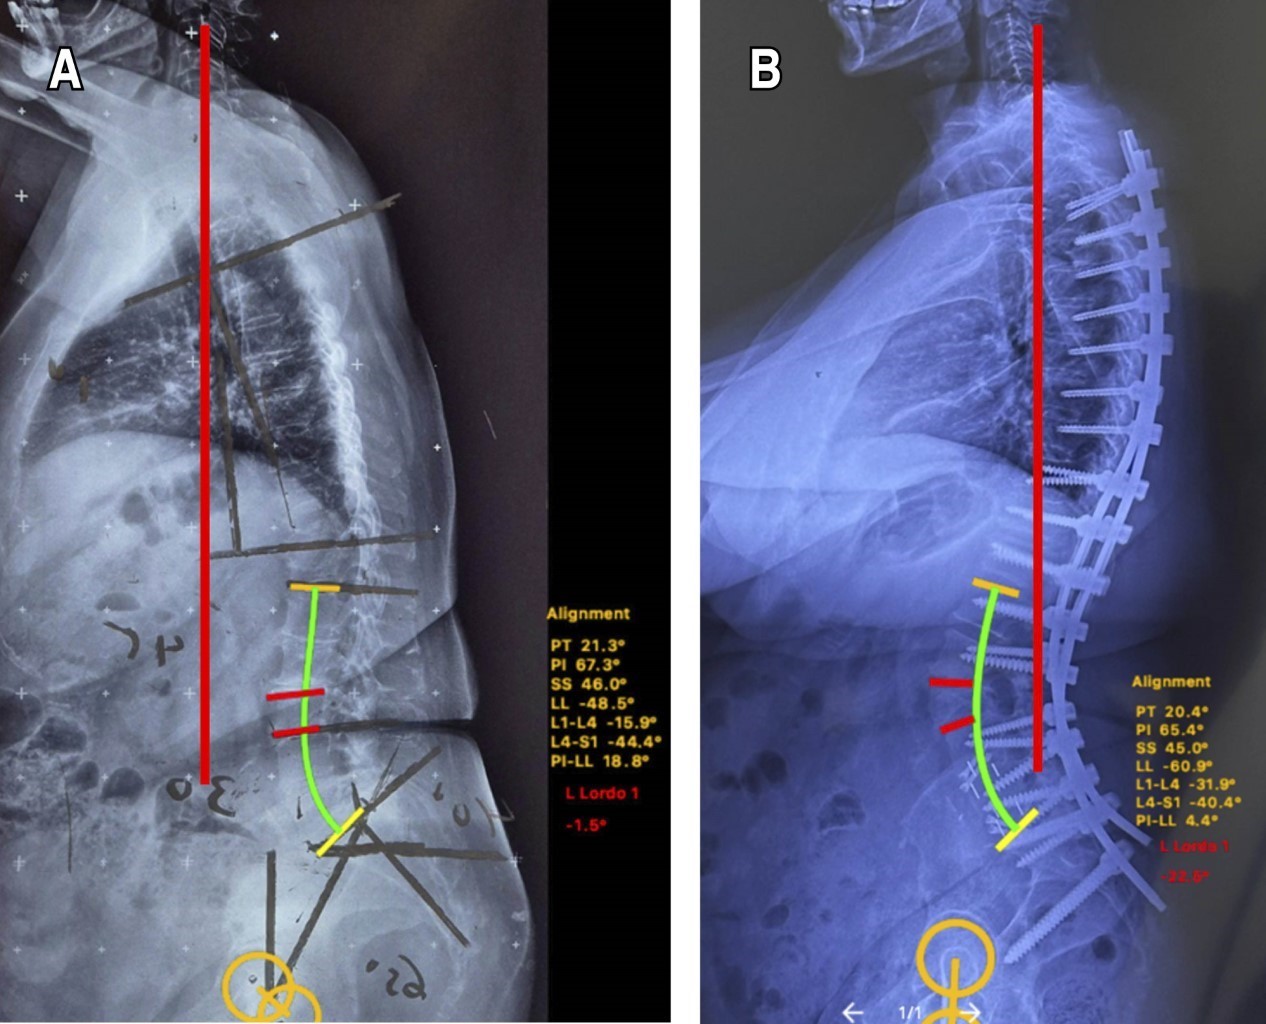

Figure 3